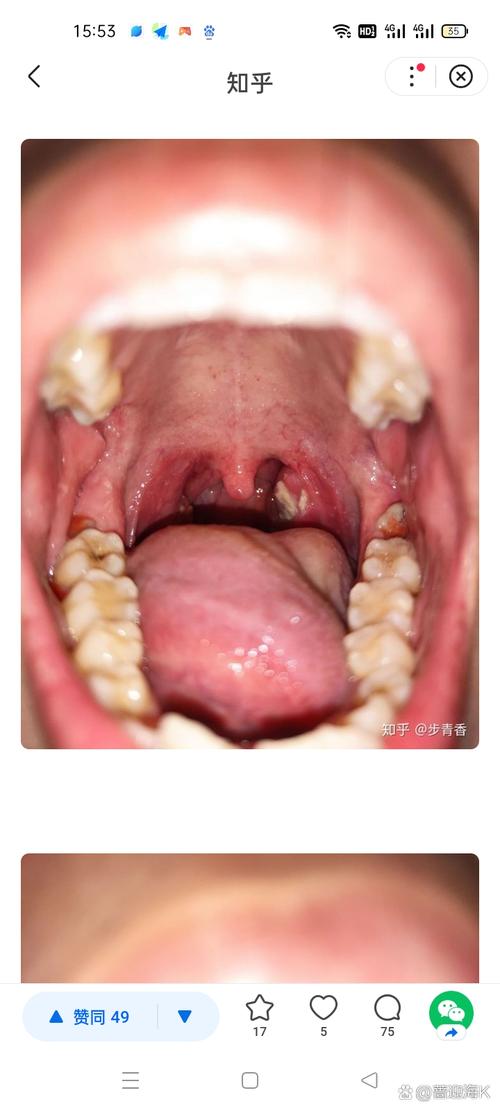

(图片来源网络,侵删)

- 特点:通常是圆形或椭圆形的浅表溃疡,表面有黄色或灰白色的假膜,周围有一圈红晕,疼痛感非常剧烈。

- 单纯疱疹病毒:这是导致扁桃体上出现“水泡”或“溃疡”的常见病毒,初期可能表现为成簇的小水疱,随后破溃形成浅表溃疡,常伴有剧烈疼痛、发热、咽喉肿痛、颈部淋巴结肿大等症状,也就是我们常说的“疱疹性咽峡炎”或“急性疱疹性龈口炎”。

| 溃疡外观 | 单个或几个,圆形,边界清,有黄白色假膜 | 可能为成簇的小水疱,后破溃成点状或片状溃疡 | 形状不规则,与创伤部位一致 |